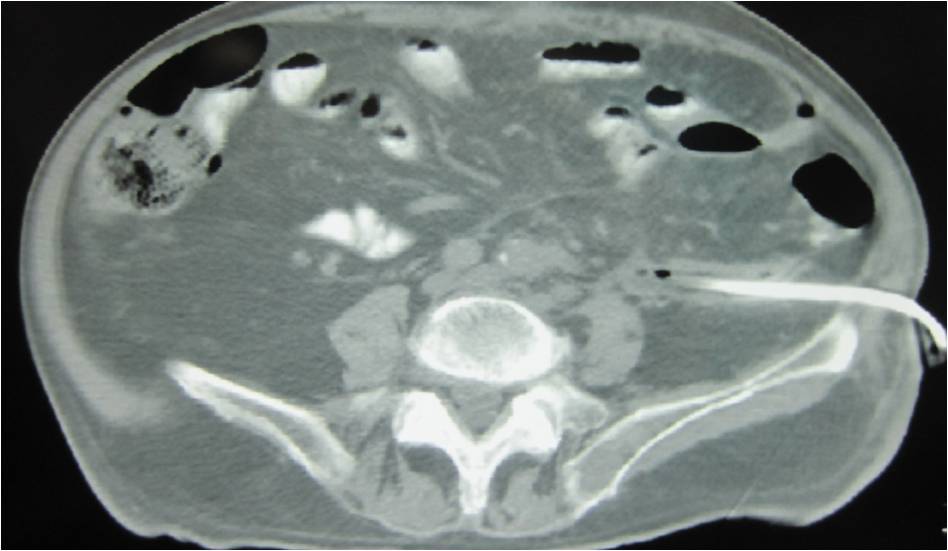

- Large abdominal abscess post- pancreatic surgery

- Successful drainage